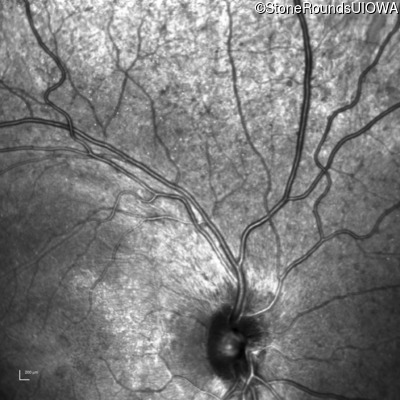

Infrared Fundus Photograph - Right - 20/25 -1

Exemplar